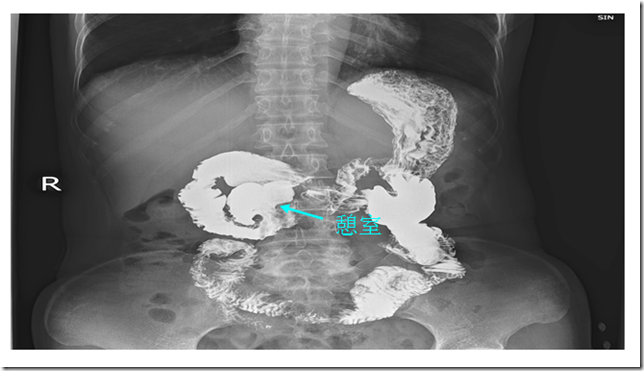

本病例X光造影影像

患者文某,女性,52岁,因反复上腹部胀痛多年,曾辗转我市多家大型综合医院就医,始终未能痊愈,饱受疼痛折磨,严重影响工作和生活。本月初于我院就诊,经胃肠道造影、CT等检查,确诊为十二指肠水平段巨大憩室。由于憩室所在位置解剖结构复杂,且憩室伸入胰腺后方,手术难度大,风险高。在何启雄副院长带领下,外科医疗团队紧密合作,认真细致研究病情,组织多学科会诊,经过充分讨论研究,制定了多套手术方案,最终成功切除憩室,患者术后恢复顺利,未发生任何并发症。此例手术成功实施,体现了我院外科医疗技术水平进一步提高,外科医疗专业建设进一步加强。

胃肠道憩室疾病简介 :胃肠道憩室是因为胃肠管壁发育不良或邻近溃疡等原因导致肌层薄弱、缺损或牵拉而形成的袋状突起。十二指肠是仅次于结肠的憩室好发部位,因十二指肠的位置特殊,此处发生憩室容易引起憩室炎、出血或梗阻,并进一步并发胆管炎、胰腺炎、胆囊炎等疾病。由于此处解剖复杂,多数憩室切除困难,多采取转流、旷置等其他手术方法,从而不能彻底治愈。